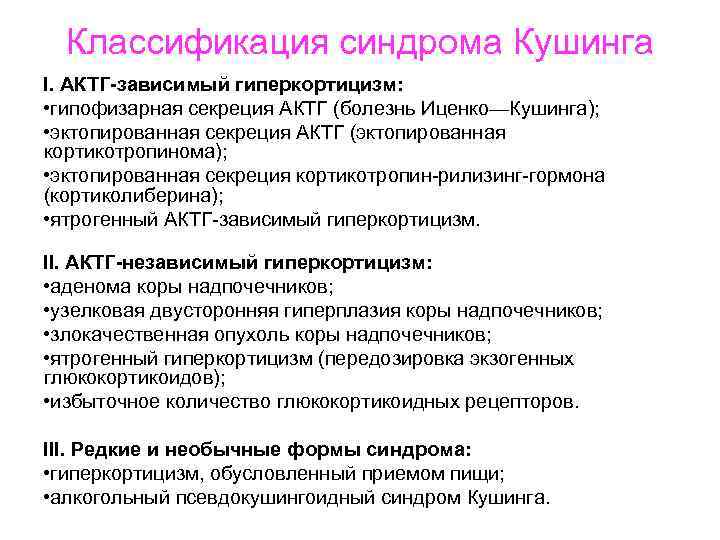

Классификация синдрома Кушинга I. АКТГ-зависимый гиперкортицизм: • гипофизарная секреция АКТГ (болезнь Иценко—Кушинга); • эктопированная секреция АКТГ (эктопированная кортикотропинома); • эктопированная секреция кортикотропин рилизинг гормона (кортиколиберина); • ятрогенный АКТГ зависимый гиперкортицизм. II. АКТГ-независимый гиперкортицизм: • аденома коры надпочечников; • узелковая двусторонняя гиперплазия коры надпочечников; • злокачественная опухоль коры надпочечников; • ятрогенный гиперкортицизм (передозировка экзогенных глюкокортикоидов); • избыточное количество глюкокортикоидных рецепторов. III. Редкие и необычные формы синдрома: • гиперкортицизм, обусловленный приемом пищи; • алкогольный псевдокушингоидный синдром Кушинга.

Классификация синдрома Кушинга I. АКТГ-зависимый гиперкортицизм: • гипофизарная секреция АКТГ (болезнь Иценко—Кушинга); • эктопированная секреция АКТГ (эктопированная кортикотропинома); • эктопированная секреция кортикотропин рилизинг гормона (кортиколиберина); • ятрогенный АКТГ зависимый гиперкортицизм. II. АКТГ-независимый гиперкортицизм: • аденома коры надпочечников; • узелковая двусторонняя гиперплазия коры надпочечников; • злокачественная опухоль коры надпочечников; • ятрогенный гиперкортицизм (передозировка экзогенных глюкокортикоидов); • избыточное количество глюкокортикоидных рецепторов. III. Редкие и необычные формы синдрома: • гиперкортицизм, обусловленный приемом пищи; • алкогольный псевдокушингоидный синдром Кушинга.